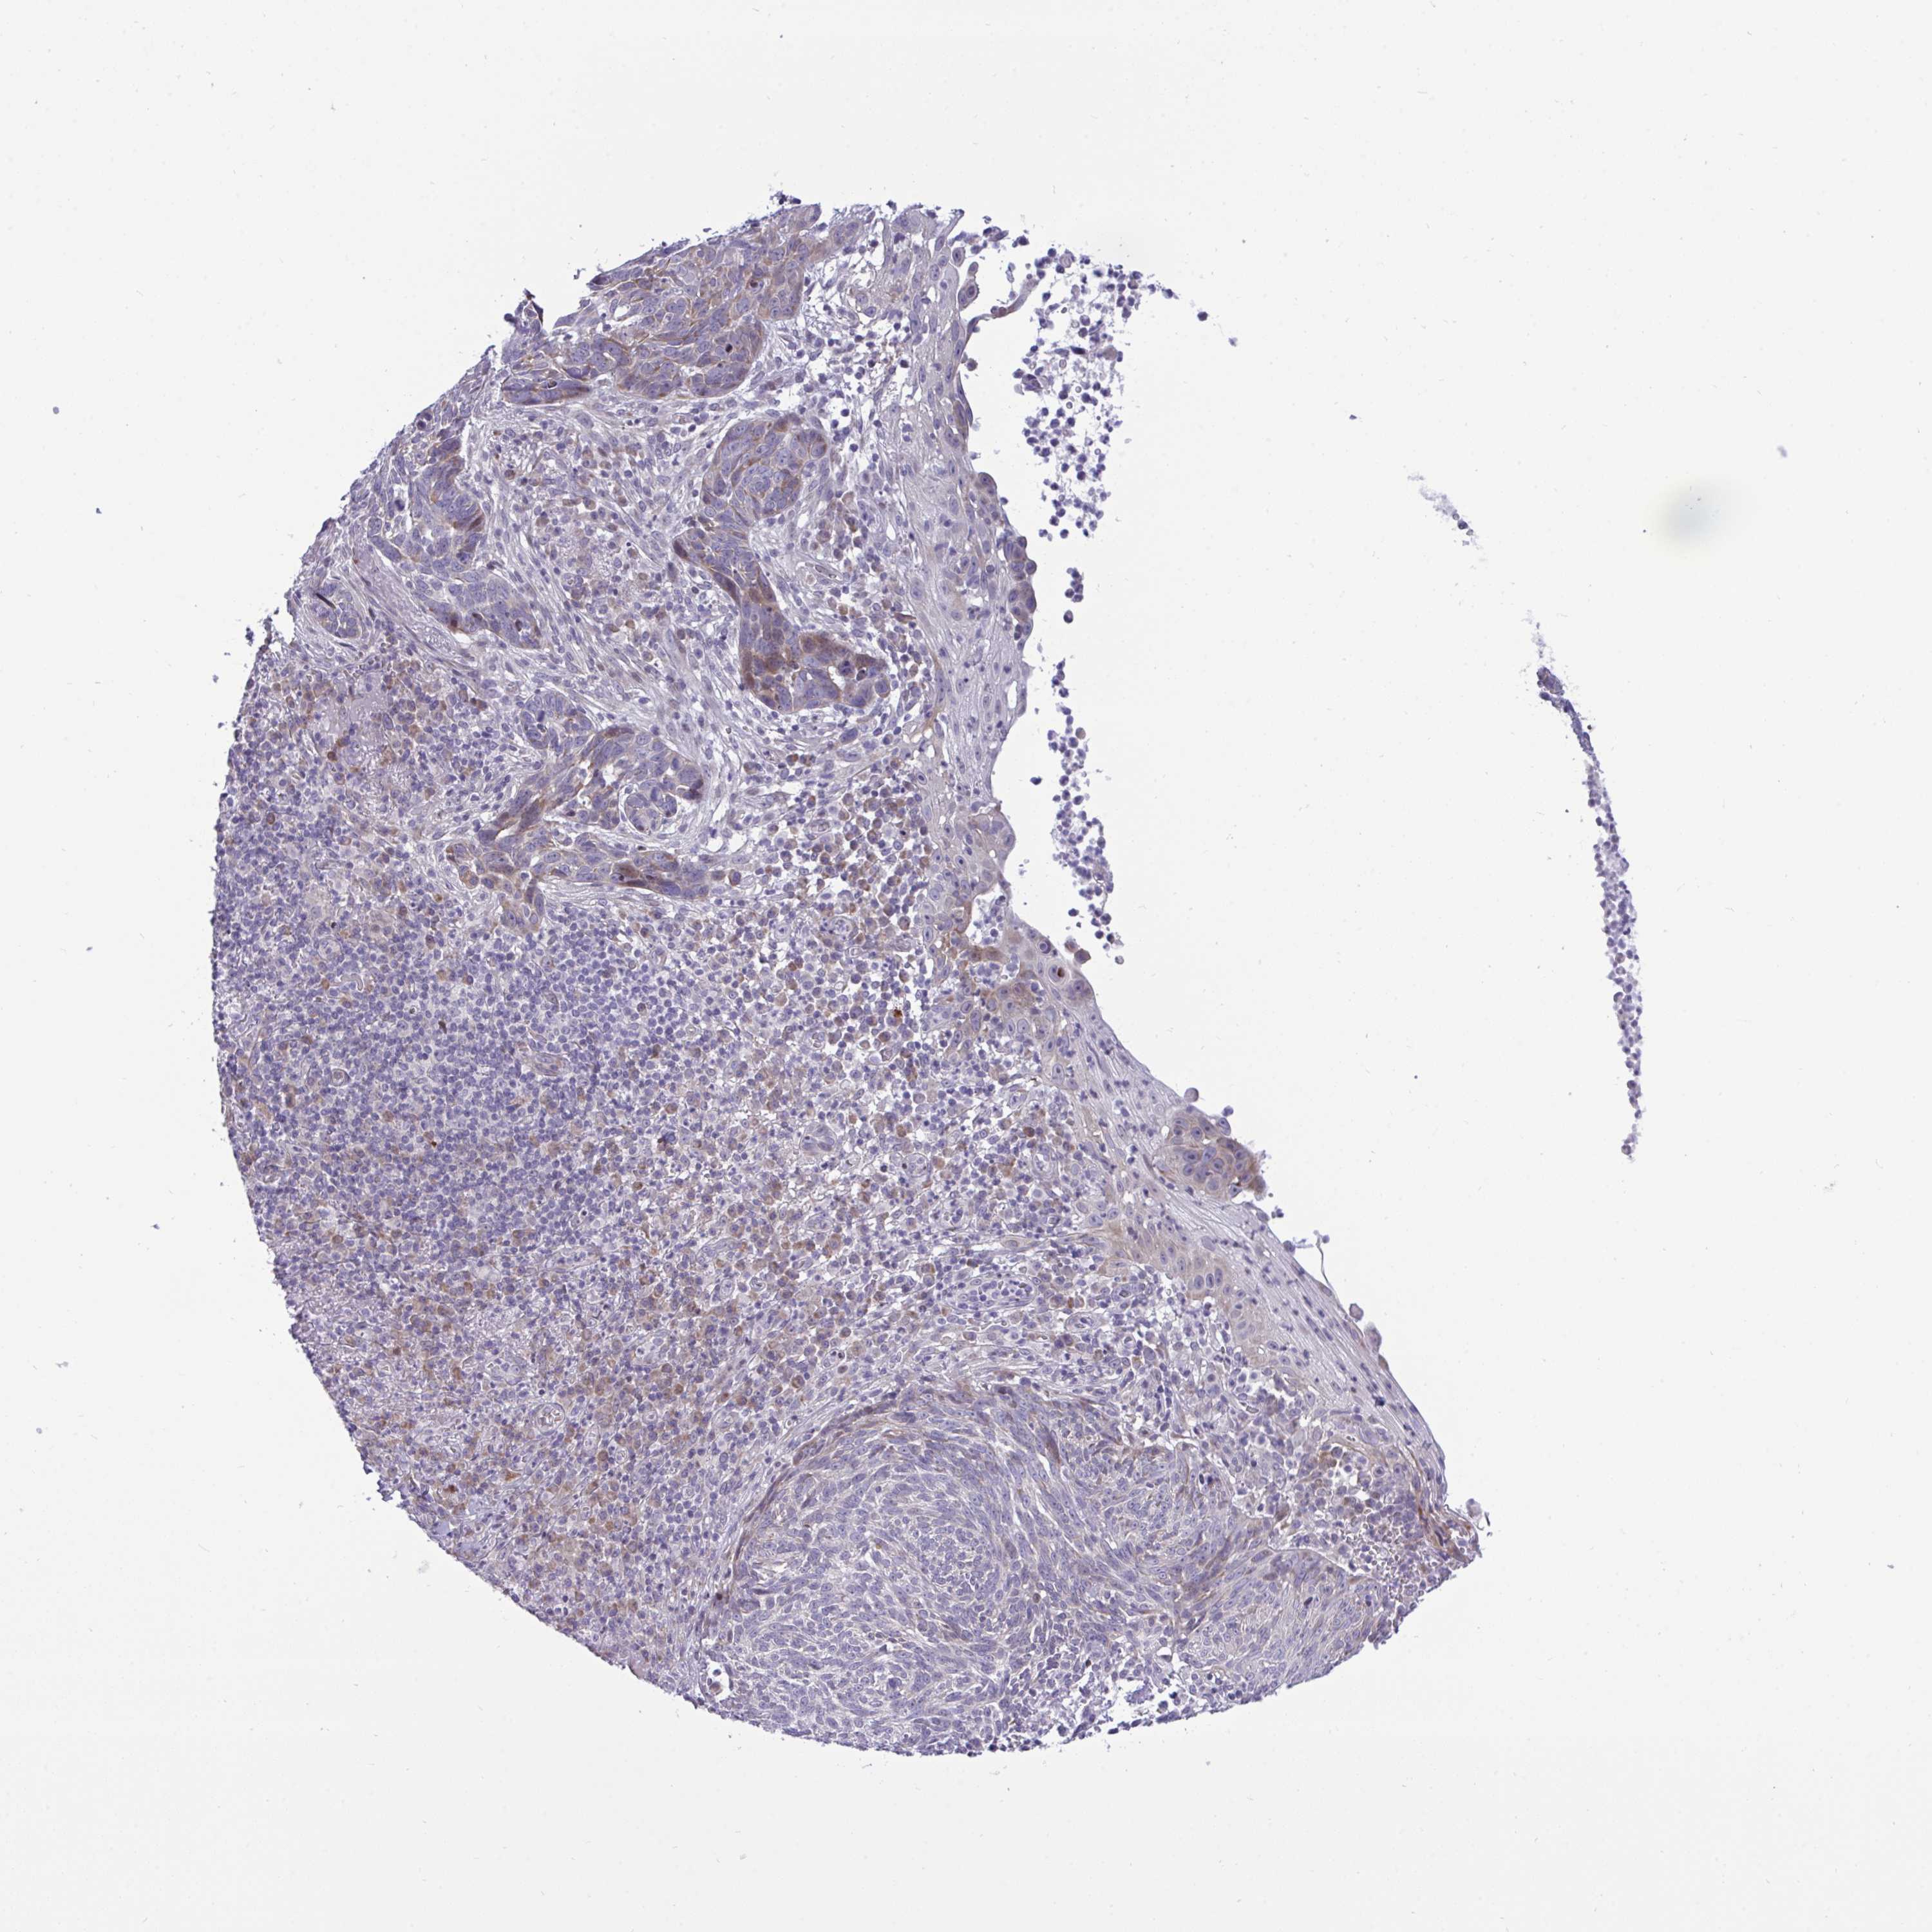

SKIN CANCER - Protein expressioni

A mouse-over function shows sample information and annotation data. Click on an image to view it in a full screen mode. Samples can be filtered based on level of antibody staining by selecting one or several of the following categories: high, medium, low and not detected. The assay and annotation is described here.

Antibody stainingi

Antibody staining in the annotated cell types in the current human tissue is reported as not detected, low, medium, or high, based on conventional immunohistochemistry profiling in selected tissues. This score is based on the combination of the staining intensity and fraction of stained cells.

Each image is clickable and will lead to virtual microscopy that enables deeper exploration of all samples and also displays staining intensity scores, fraction scores and subcellular localization as well as patient and tissue information for each sample.

Antibody HPA056555

Staining

High

Medium

Low

Not detected

Intensity

Strong

Moderate

Weak

Negative

Quantity

>75%

75%-25%

<25%

None

Location

Nuclear

Cytoplasmic/membranous

Cytoplasmic/membranous,nuclear

Basal cell carcinoma

Squamous cell carcinoma, NOS